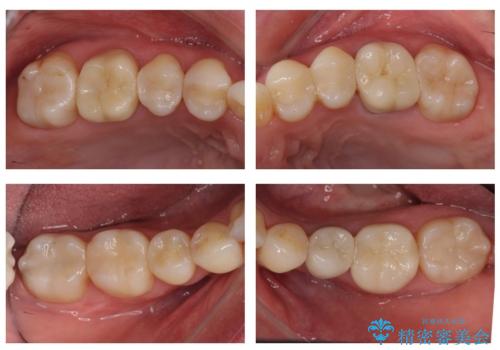

全体的な虫歯治療 銀歯をセラミックに

- 当院で矯正治療後、虫歯治療を一通り行いました。

虫歯にならないようにするためにはしっかり精度の高い治療を行うことが大事です。

それと同時に歯ブラシをしっかりおこなうことや、食生活にも気を付けることが重要です。

毎食後の歯ブラシ、フロス、歯間ブラシをしっかり行うようにすると効果的です。